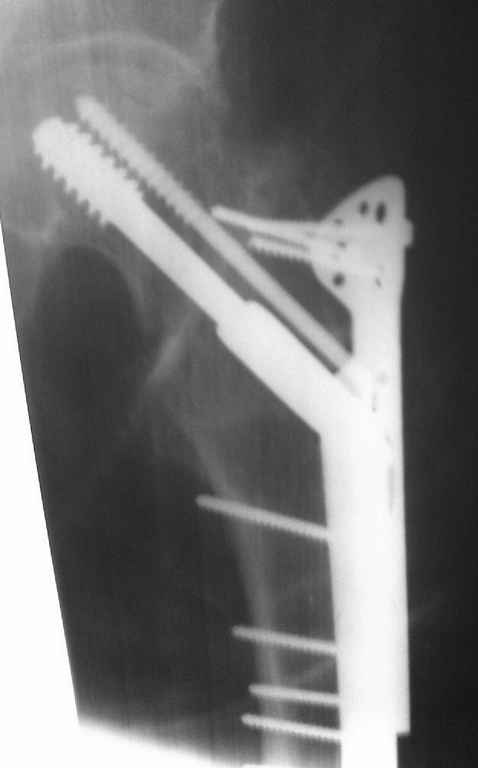

Безусловно надо оперировать. Метод фиксации лучше выбрать такой которым Вы лучше владеете, и который позволяет техническое оснащение вашего учереждения. Я бы поставил DHS с деротационным винтом, возможно и без вертельной накладки.

В отличии от трансцервикального или субкапитального вероятность развития аваскульрного некроза относительно низкая т.к. кровоснабжение головки бедра по ретинакулярным сосудам сохранено. Фиксация трехлопастным гвоздем не эффективна т.к. гвоздь да и шурупы не обеспечивают угловой стабильности. Кроме этого, техника установки трехлопастного гвоздя может повредить оставшиеся целыми ретинакулярные сосуды. Наиболее подходящие фиксаторы должны иметь фиксированый угол - шуруп с диафизарной пластинкой типа DHS или любой интрамедуллярный гвоздь имеющий блокирующие шурупы которые можно ввести в шейку бедра типа PFN, Reconstruction nail, Gamma или др. Скелетное вытяжение тоже может сработать, только, конечно, значительно труднее достичь редукции и опять же при перерастяжении возможно нарушение кровообращения головки бедра.

В мультицентровой обработке материала 844 переломов шейки бедра (Bernes et al), осложнения вследствие применения DHS составили 57% и поэтому у многих отношение к этим имплантам скептическое.

Большинство осложнений связано с применением неадекватных фиксаторов, то есть не предназначенных для фиксации чистых переломов шейки бедра, например DHS, CHS, Blade Plate и разных других реконструктивных интрамедуллярных гвоздей, которые предназначены для лечения чрезвертельных переломов.